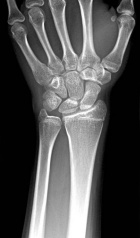

15 year old female with soft tissue mass over right hypothenar eminence.

Referred by outside physician after excision of a presumed ganglion cyst.

Zoom image: Radiological image Radiological image.